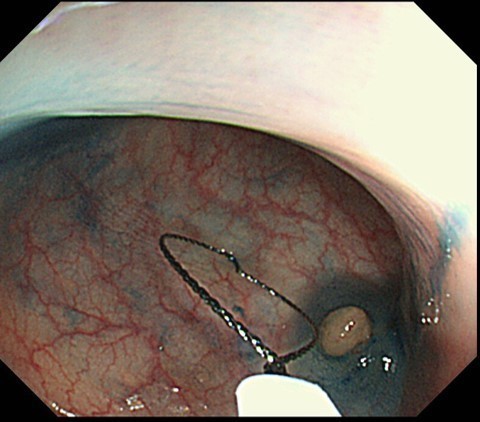

国立がんセンター中央病院や群馬中央病院 など大病院と同等の最新の内視鏡診断・  治療機器を導入しています。最新の内視鏡はハイビジョンで病変の超早期発見に非常に 有用です。さらに病変発見や診断に有用な オリンパス社のNBI(narrow band imaging)富士フイルム社のレーザー内視鏡を導入。世界最高水準の成績を誇る国立がんセンター中央病院で実証してきたそれぞれの特徴を最大限にいかしてみなさんの検査を行います。

日帰り内視鏡治療

当クリニックでは大腸ポリープ・病変発見時に一度で検査・治療を行うことができます。大腸内視鏡を行ってもポリープがあると あらためて別の病院でもう一度下剤をのみ内視鏡治療を受ける必要となる施設もあります。一度で治療までできることは体力も時間も金銭的にも負担が少なくなります。

少しでも検査を受けられるみなさんの負担が少なくなるよう工夫し、当クリニックでは大腸ポリープ・病変発見時に一度で検査・治療を行うことができ、治療のあとゆっくり休むことができる体制を整えております。また遠方の方、トイレが不安な方には院内で検査前の下剤をのむ環境も整っております。一度ご相談ください。